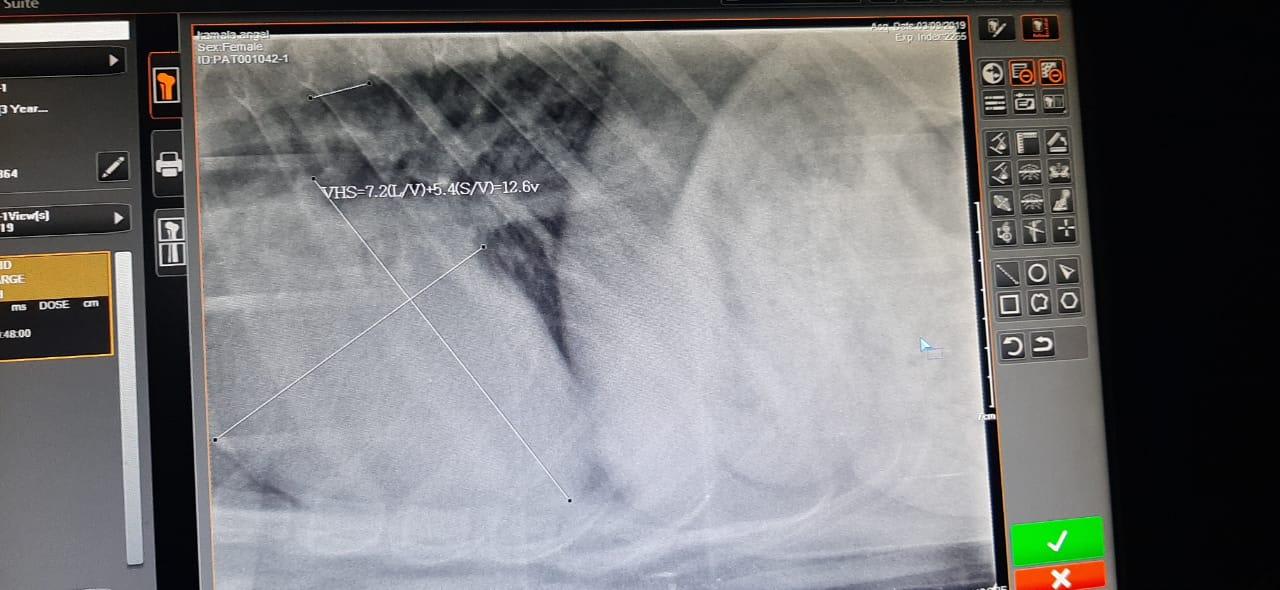

My pet had a seizure like thing yesterday. Today we had taken her to the vet. He did a heart x-ray. He said the VHS is 12.6. My pet was very nervous and scared when we were handling her during the X-ray. She was breathing very loudly and in speed because we were holding her legs and face. Is the high rate in VHS because of that? What is the estimated VHS for Labrador retrievers. Is it dangerous? Is the high rate in VHS because of her being nervous? I'm extremely worried and scared. Please help.

Hello, and thanks for your question on Petco Pet Education Center, formerly Petcoach. VHS or Vertebral Heart Score is a measure of the size of the heart, and would not be related to the dog's respiratory rate or level of anxiety. Normal VHS usually ranges from 8.5-10.5, so Angel's VHS is a bit high. There are a number of things that could cause a heart to become larger than normal, so to have more information about what might be causing the increased size of Angel's heart, an echocardiogram (ultrasound of the heart) should be performed. Your primary vet should be able to help guide you to a specialty vet clinic that would be able to perform an echo. Hope this helps, and good luck to you and Angel.